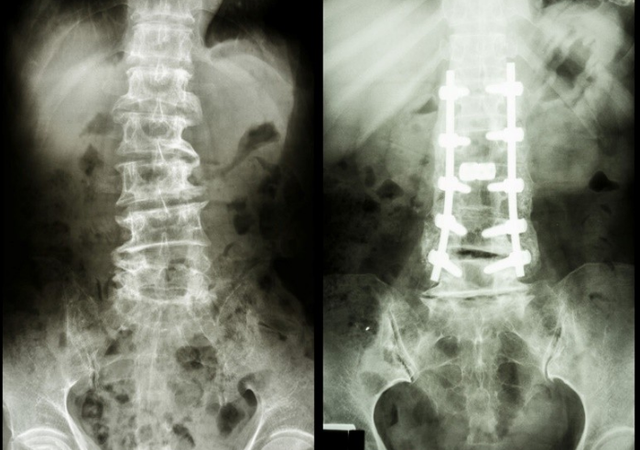

社会的不断发展 , 老龄化越来越严重了 , 以中老年人为主要目标群体的诸如骨质疏松相关的病症越来越普遍了;根据研究调查显示 , 逐渐可以看出来人们的骨质疏松的平均年龄正在逐渐的减少 , 骨质疏松的症状越发的年轻化了 。

目前临床上骨质疏松的类型慢慢从原发性的骨质疏松开始偏向继发性的骨质疏松转变 , 这样的转变意味着 , 骨骼的健康越来越受外部环境的影响了 , 像我们自身的一些饮食 , 运动 , 生活习惯都会影响着我们的骨骼健康 。